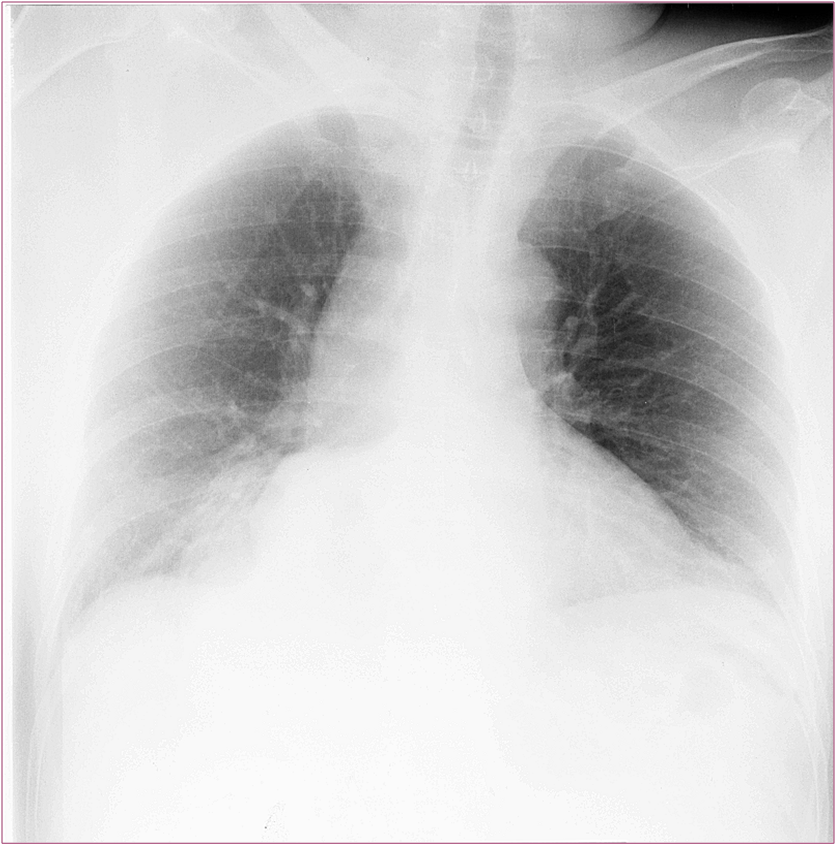

Image Image

Fig.8., 9.:Incarcerated hiatus hernia

A middle aged female with eight day history of abdominal pain was emergently admitted to the surgery department. The chest and abdominal radiographs showed no alteration, thus the patient was released home. Four days later she was readmitted to a different hospital where the upper GI series revealed an incarcerated hiatus hernia. Surgical exploration confirmed perforation of the ulcerated wall in the incarcerated gastric segment. Second review of the initial chest x-ray a found a right lower mediastinal soft tissue mass that had already been present at the time.

Upper GI series must be always performed in these patients!